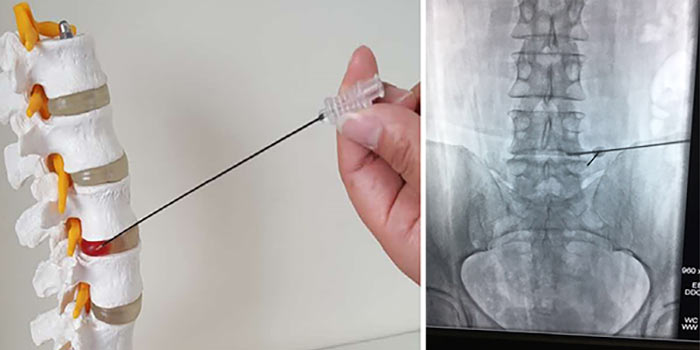

Диагноз подтверждается биопсией. Врач получает фрагмент опухолевой ткани и отправляет его в лабораторию для цитологического и гистологического исследований, а также молекулярно-генетических анализов. Материал для биопсии может быть получен различными способами:

- Чаще всего проводят пункционную чрескожную биопсию с помощью иглы под контролем рентгена.

Хирургическое лечение

Для стабилизации позвонков и уменьшения болей может быть выполнено миниинвазивное вмешательство. В позвонок вставляют иглу и заполняют объем костной ткани специальным цементом.